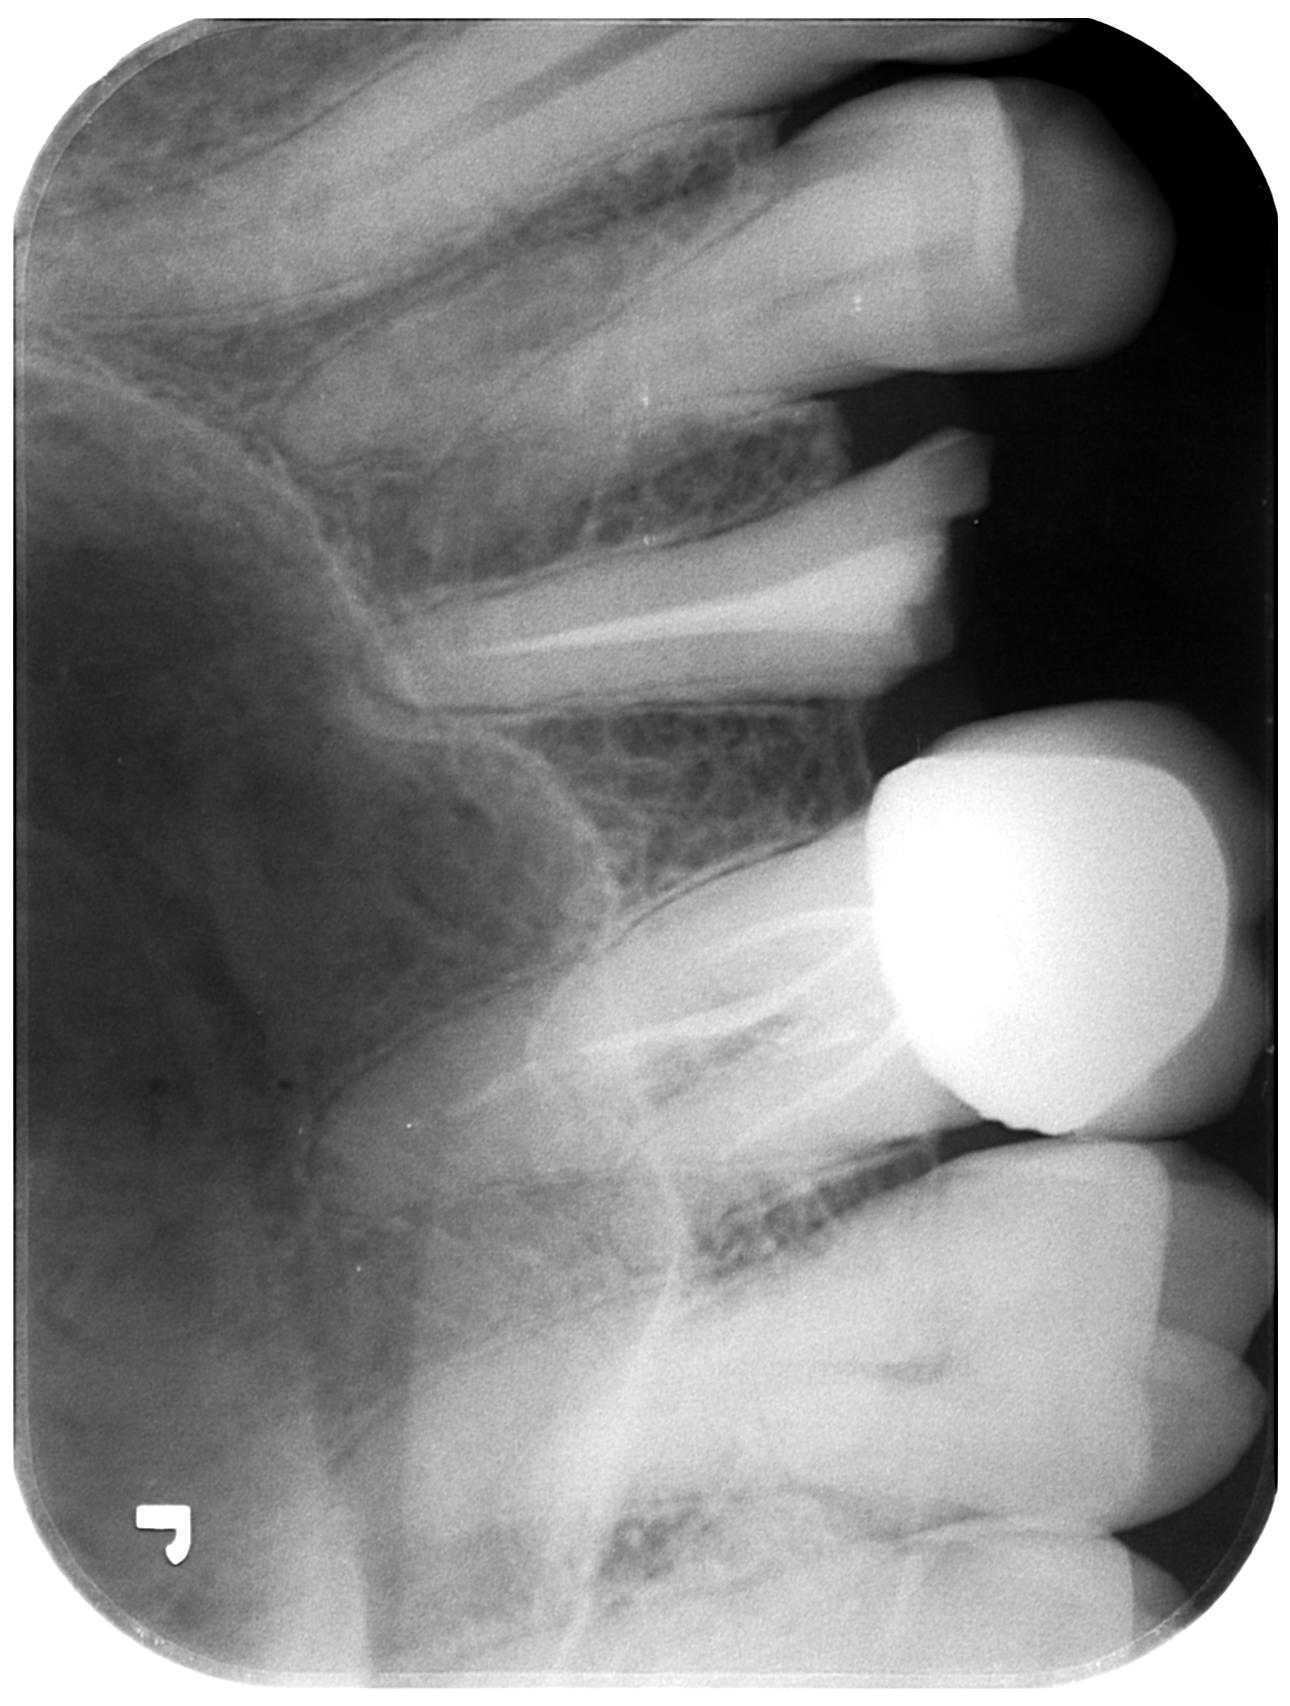

Post & Core / CLP / Crown or Implant

- Post & core / CLP / crown

- Extraction & Implant